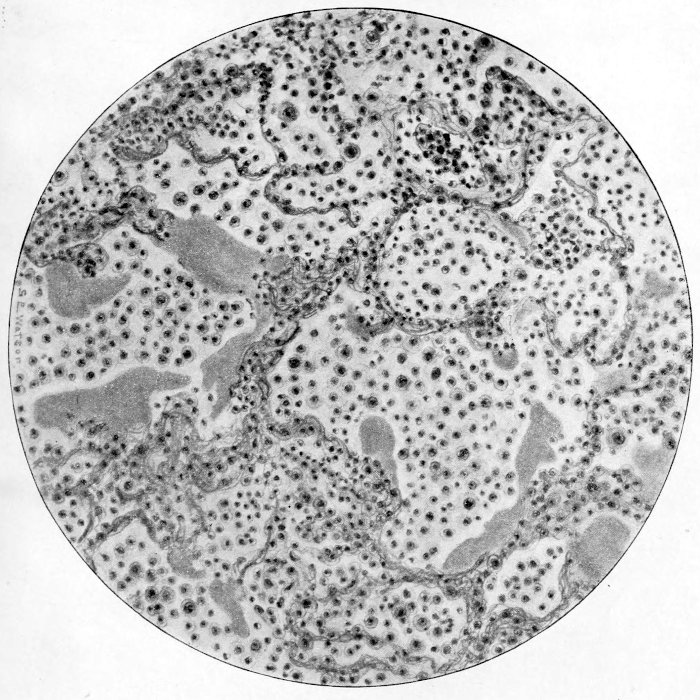

subscribe to our email newsletter to hear about new eBooks.